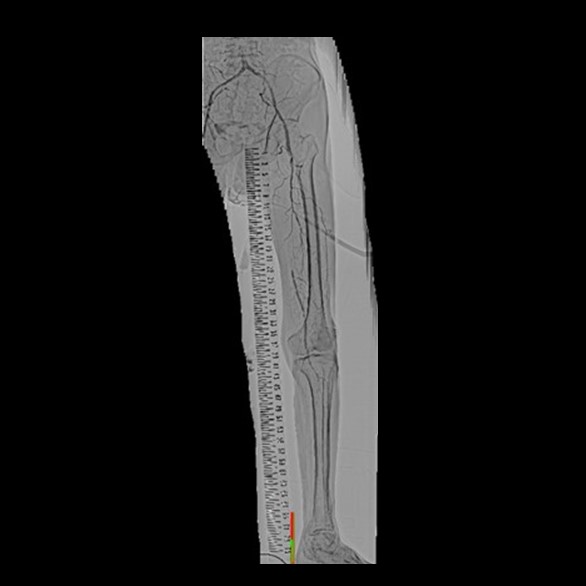

四肢血管撮影

四肢の血管造影では、腕や足などの動脈硬化などで狭くなった血管に対してカテーテルを挿入し風船やステント等で狭窄部位を拡張し、抹消への血流を改善する治療を行います。

左下肢動脈造影

左浅大腿動脈閉塞

術後動脈造影